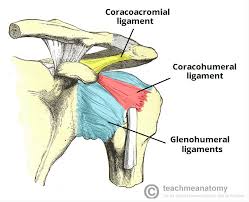

Coracoacromial ligament

Glenohumeral ligament